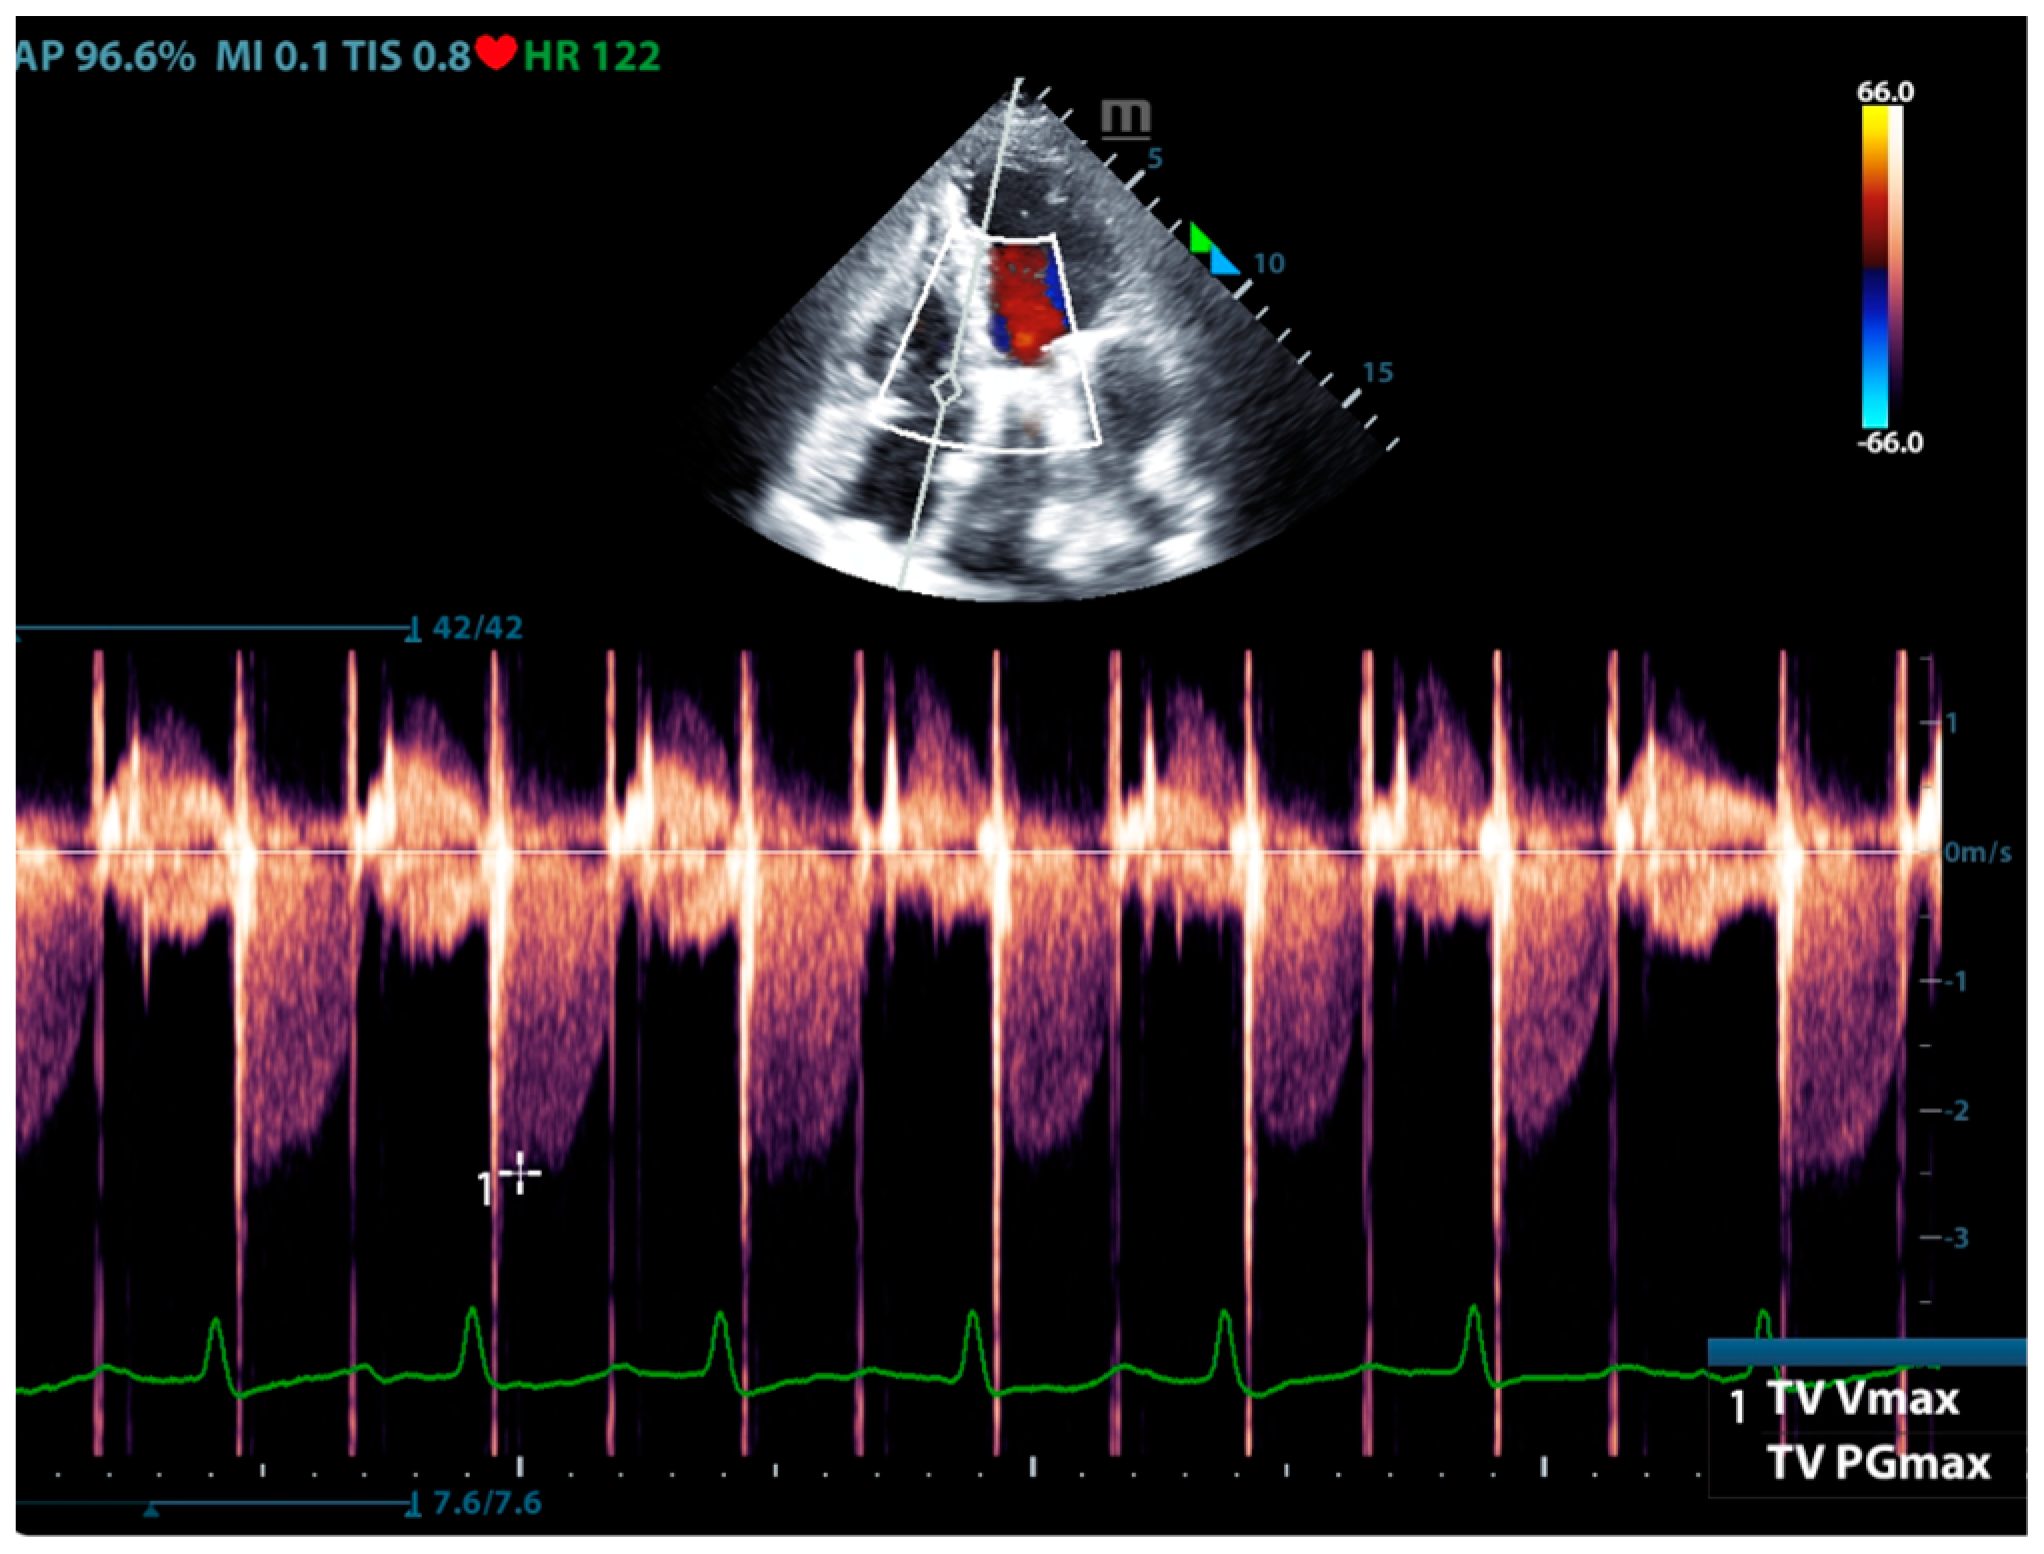

Physicians can assess pulmonary artery pressure quantitatively with point-of-care ultrasound. According to Bernoulli’s principle, the systolic pressure and diastolic pulmonary artery pressure can be estimated, respectively, by measuring the maximum regurgitation velocity of the tricuspid valve and the pulmonary valve. The maximum regurgitation velocity of the tricuspid valve (TVR Vmax) can be measured in the apical four-chamber view (Figure 6), and the maximum velocity of the pulmonary artery valve regurgitation (PVR Vmax) can be measured in the pulmonary artery long-axis view (Figure 7). Physicians can estimate pulmonary artery systolic pressure (PASP), diastolic pressure (PADP), and mean pulmonary artery pressure (mPAP) based on the ultrasound-measured TVR Vmax and PVR Vmax by the following formulas:

PASP = TVR Vmax2 + RAP(CVP)

PADP= PVR Vmax2 + RAP(CVP)

mPAP = 1/3 ∗ PASP + 2/3 ∗ PADP

Figure 6.

The ultrasound measurement of the maximum velocity of tricuspid valve regurgitation.

This can not only be used for the diagnosis of pulmonary hypertension but also for continuous and dynamic evaluation of pulmonary artery pressure [26]. It should be noted that the use of tricuspid regurgitation velocity to estimate pulmonary artery pressure with ultrasound Doppler has limitations. When the patient has severe tricuspid valve disease or severe right heart dysfunction, using the maximum tricuspid regurgitation velocity may underestimate the pulmonary artery pressure. Therefore, the evaluation of pulmonary hypertension should be combined with other ultrasound signs of the right ventricle, pulmonary artery, inferior vena cava, and right atrium.